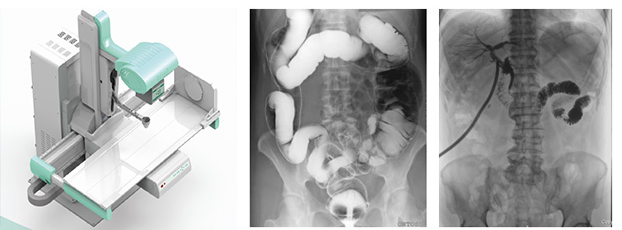

醫(yī)用DR,以其高質(zhì)量圖像和高工作效率正逐漸替代現(xiàn)在傳統(tǒng)X線攝影技術(shù), 成為當(dāng)今數(shù)字X線攝影技術(shù)的代表,它可以對于人體內(nèi)部組織進(jìn)行透視、檢查,從而快速診斷患病情況,及時給予治療。作為一種全新X線成像技術(shù),醫(yī)用DR使整個放射科特別是常規(guī)放射診斷的工作效率和經(jīng)濟(jì)效益得到明顯提高。

醫(yī)用DR是臨床應(yīng)用比較多見的放射科設(shè)備之一,其利用X射線對物體的穿透性原理,控制X射線用于對人體組織放射檢查和放射治療。如果您想購買普愛醫(yī)療的醫(yī)用DR,或了解產(chǎn)品具體參數(shù),歡迎聯(lián)系我們。